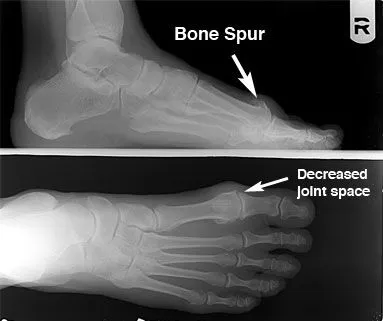

Diagnosis: hallux_rigidus3.jpg

The sooner this condition is diagnosed, the easier it is to treat. Therefore, the best time to see a foot and ankle surgeon is when you first notice symptoms. If you wait until bone spurs develop, your condition is likely to be more difficult to manage.

In diagnosing hallux rigidus, the surgeon will examine your feet and move the toe to determine its range of motion. X-rays help determine how much arthritis is present as well as to evaluate any bone spurs or other abnormalities that may have formed.